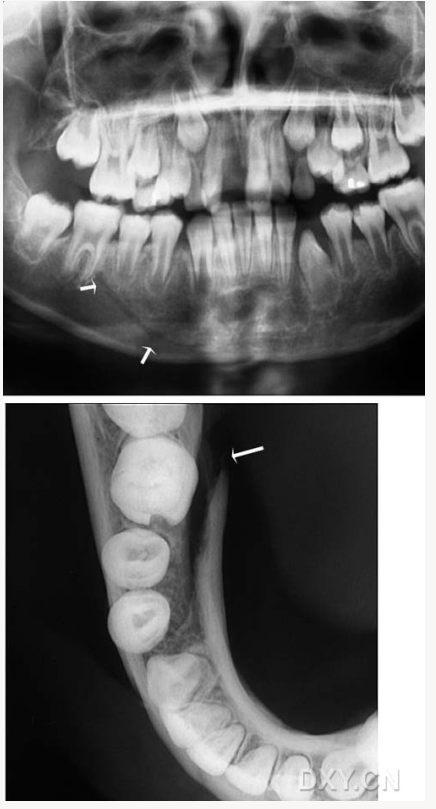

含牙囊腫

牙源性角化囊腫